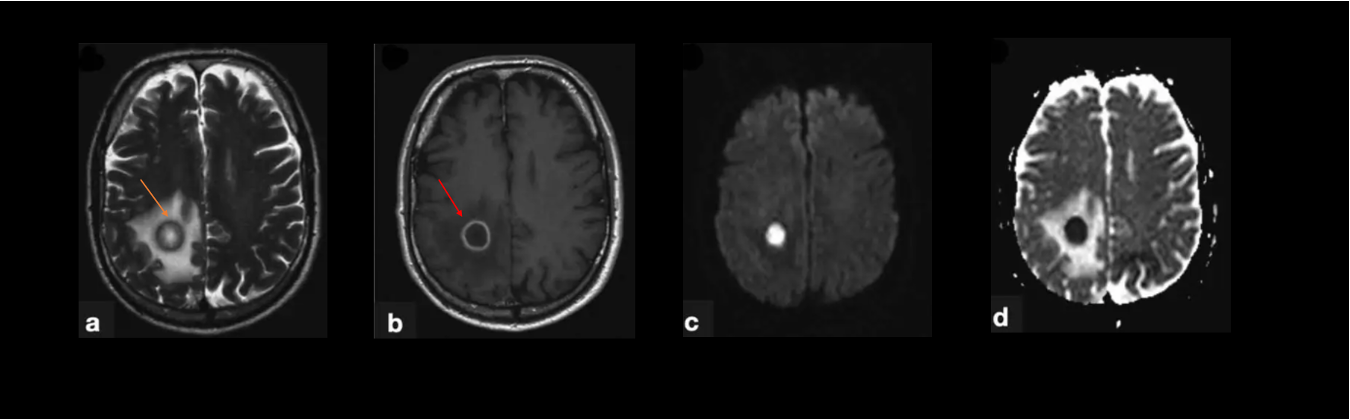

A 67-year old woman with chronic hypertension, hyperlipidemia and diabetes mellitus non-compliant to medication presented with a 10-day history of recurrent visual phenomena in the left visual field. She described stationery multi-coloured flashing lights which decreased in intensity, brightness and size after 3 minutes. She was alert and conscious during attacks. There was no limb jerking. Neurological examination was normal with no visual field defect. Capillary glucose was 28.1 mmol/L, Hba1c 9% and B-hydroxybutyrate < 0.1. She was treated with actrapid 8 units, glipizide 5 mg BD and empagliflozin 12.5 mg OM. Interictal electroencephalogram was normal with no epileptiform activity. Brain magnetic resonance imaging revealed restricted diffusion in the right occipital cortex with corresponding cortical thickening and increased FLAIR signal with subtle hypodensity on GRE sequence. Her visual symptoms improved dramatically with hydration and diabetic control. She was treated with a short course of keppra. One month later repeat MRI brain showed resolution of the DWI and FLAIR abnormalities.

Initial dwi

D